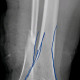

Saya cukup bingung dok untuk menentukan garis fraktur pada os tibia pasien, apakah ini termasuk fraktur inkomplit dok? Karena saya tidak melihat diskontinuitas tulang sejelas saya melihat diskontinuitas pada fibula

Alo dokter, fragmen tibia ada di distal melibatkan metafisis dan epifisis, ini termasuk fraktur intraartikuler

Alo dokter, setuju dengan pendapat dr.Yohannes Toban, saya melihat adanya garis fraktur pada bagian distal tibia daerah yang kita sebut dengan tibial plafond (pilon), dan medial maleolus nya. Baiknya supaya lebih jelas, boleh menambahkan rontgen Ankle joint.